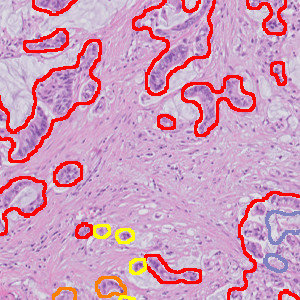

Figure 2

Metastases are identified as High Probability (red), Medium Probability (orange), Low Probability (yellow) and the largest is highlighted and measured.

Figure 4

The remaining metastases in the image are reviewed as necessary, showing High Probability (red), Medium Probability (orange) and Low Probability (yellow).